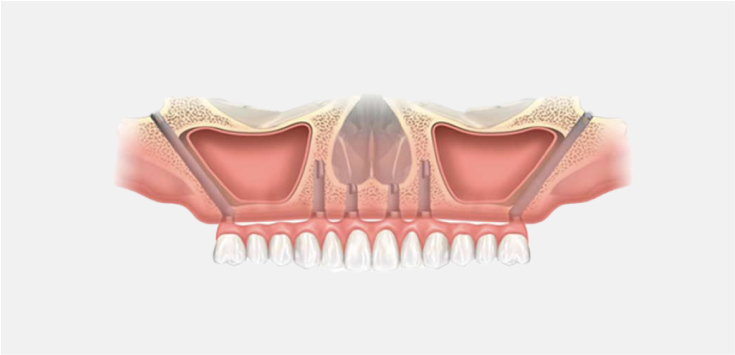

失った歯を一気に取り戻す

オールオン4インプラント

4本〜6本のインプラントで全ての歯を取り戻す治療です。 見た目・噛み心地・高い耐久性を実現します。歯がボロボロ、総入れ歯の方も、1回の手術でしっかり噛める歯を取り戻すことが可能です。

骨を失っても、噛める歯を再び

ザイゴマインプラント

ザイゴマインプラントは頬骨にインプラントを埋込することで、骨移植を必要としない治療です。通常のインプラントやオールオン4が難しい方も、治療を諦める必要はありません。